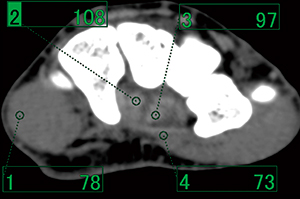

VR画像での腱・靭帯の描出を目的としたCT撮影を行う場合,画像ノイズの少ない画像を得ることが重要である。通常,骨・関節の診断を目的とした場合は120kV,30~60mAs程度で撮影を行っているが,腱・靭帯描出を目的とした場合は100~200mAsまで線量を上げて画像ノイズを少なくする必要がある(図1)。

また,135kVの高管電圧を使用すると,FOV中心付近にある腱・靭帯のCT値低下に比べて周囲の筋肉のCT値低下が大きくなるため,相対的にコントラストを上昇できる。検査部位にもよるが,VR画像を作成する上で腱・靭帯と筋肉の分離がしやすくなる(図2,3)。

図1 撮影条件と手指屈筋腱の描出能の差異

骨のVR画像であれば30mAsで十分に作成可能であるが,腱の描出は難しいため線量を上げる必要がある。

図2 120kVにおける屈筋腱と周囲組織のCT値 |

図3 135kVにおける屈筋腱と周囲組織のCT値 |